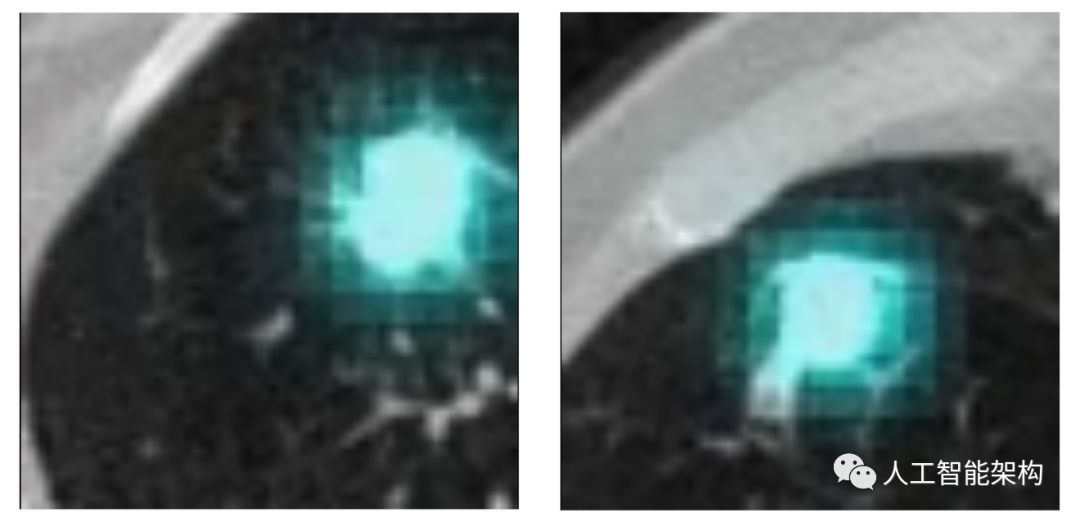

下图显示了训练期间不可见结节的3D特征图。基于每个位置的像素对恶性肿瘤的贡献来对图像进行着色,其中通过黑化图像的立方体并记录恶性程度的变化来估计其贡献。